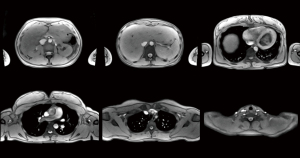

Figure 2 and Video 2 (at 19 fps) show T1-weighted images of the thorax and upper abdomen (for details see Table 1). In order to properly deal with cardiac and respiratory movements within individual cross-sectional images of the heart and lung, emphasis is placed on a sufficiently short measuring time of about 50 ms. This is best accomplished with T1 contrast and spoiled FLASH sequences, whereas refocused FLASH versions suffer from phase discontinuities in the presence of rapidly moving spins (e.g., in the blood pool). Figure 3 and Video 3 (at 13 fps) present T1-weighted images of the abdomen and pelvis with interleaved fat suppression (see Table 1). Such scans are less prone to rapid body movements and therefore allow for slightly longer acquisition times that improve SNR and include extra time for a chemical shift selective (CHESS) fat suppression module (13,14) as a frequent diagnostic option.